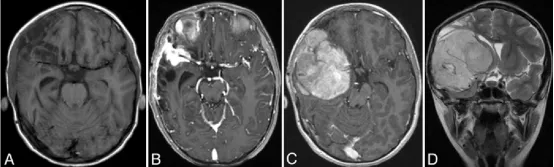

图2. A:弹簧圈栓塞术后1.5个月轴位T1加权平扫MRI,显示右额叶残余出血灶周围脑组织软化;B:术后11个月轴位T1加权增强MRI,显示右侧外侧裂区一2.3×2.7×1.8厘米(前后径×横径×头尾径)明显强化软组织肿块,包绕MCA三分叉并累及邻近硬脑膜;C、D:术后13个月轴位T1增强(C)与冠状位T2加权(D)MRI,提示肿块增大至8×7.2×7厘米,包绕大脑中动脉,侵犯前、中颅窝,伴占位效应、中线移位及硬脑膜受侵;E:右侧颈内动脉造影右前斜位片,见MCA远端M1、M2分支变细及肿瘤染色;F:右侧颈内动脉造影动脉期斜位片,显示动脉瘤部位弹簧圈移位。